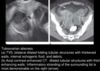

tuboovarian abscess on U.S

A